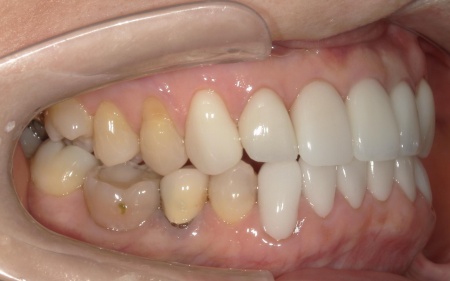

まず、左上前歯2本と左右下前歯2本の古い被せ物と土台を除去してから再根管治療を行い、ファイバーコアで土台を作ります。

続いて、新しい被せ物やポーセレンラミネートベニアの装着をするため、各部位の型取りを行いました。

後日、完成した被せ物やポーセレンラミネートベニアを装着し、見た目や使用感に問題がないことを確認して、治療を終了しています。